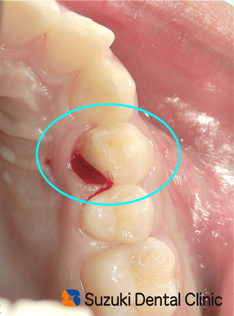

スポーツ 事故 歯が割れたサッカー選手の高校生が、来院しました。 「3日前に歯が割れた。噛んでも、息を吸っても痛む」とのこと。 プレー中に歯を強く噛みこんだことが原因で、歯(犬歯の奥となり)が二つに割れていました=写真。患者様のご家族からは「神経を抜かないとダメですか?」と質問を受けました。

歯が割れた 神経 痛む 割れた歯片は、歯肉より深くにまで達していました=写真。歯片を取ったあと、歯の神経を残せるか? 出血した歯肉部はどう対処するべきか? 的確な診断が、迫られます。そこで選んだ手法としては

○歯の形を整え、神経を残す切削術

○歯茎の整形手術

この2つの施術を麻酔下のもとで行いました。